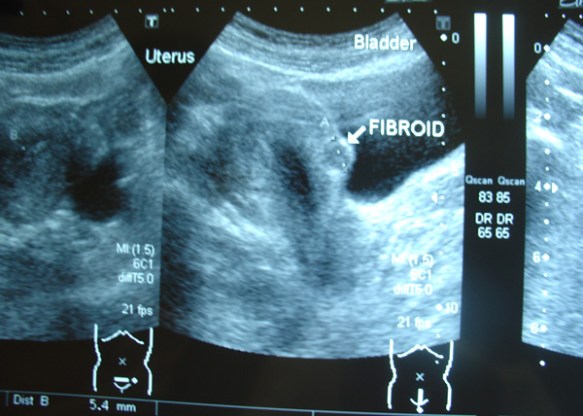

But it was not to be. In August 2023, Rina had a laparoscopic surgery in a private hospital in Jakarta. The histopathology report confirmed:

• Salphingitis – inflammation of the left and right fallopian tubes.

• Leioyonma (also referred to as fibroids or myomas).